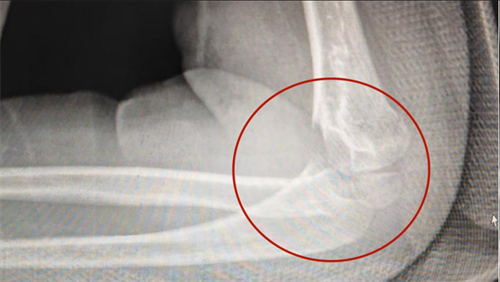

康复医学科诊室,副主任医师陈琛检查发现,李远的左肘关节弯曲只能到95°(正常 150°),伸直卡在 50°(正常 0°),活动范围不足正常三分之一,如同生锈的门轴被死死卡住。结合X 光片明确诊断为“创伤后肘关节僵硬”。